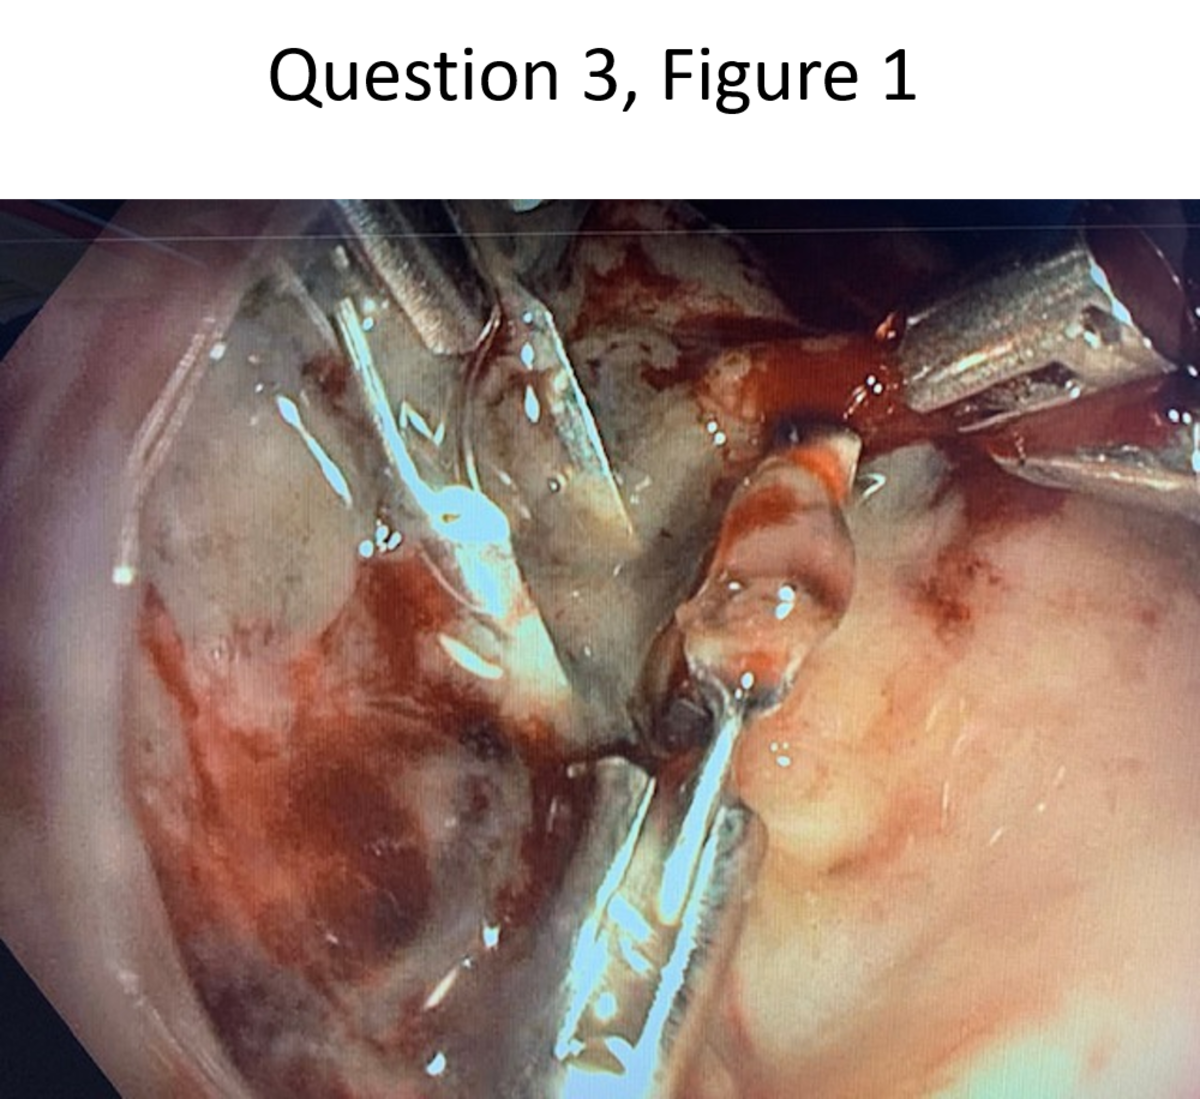

An 84-year-old woman with a remote history of possible ulcer disease presented to the emergency department with 5 days of melena following a week’s intake of an NSAID for low back pain. She reported no other significant past medical history, and no cardio-respiratory complaints; the physical exam is normal. Initial hemoglobin is 7.5 g/dL (normal: 12-16 g/dL), with platelets of 375,000/µL (normal: 150,000-350,000/µL), and an INR of 1.03 (normal: <1.4). After stabilization and transfusion of 1 unit of packed RBCs, an EGD was performed. A 2-cm duodenal ulcer with a very firm fibrotic base was noted and was treated with epinephrine injection and endoclips. The next day, the patient has a bout of red blood hematemesis and after stabilization, an EGD is repeated. Epinephrine injection, thermal coagulation, and further clips application are attempted but there is persistent bleeding (endoscopic appearance shown in the figure). Over-the-scope clip expertise is not available at your institution. What would you do now?

A

• Hemostatic powder

• excellent in achieving immediate hemostasis cannot be sole tx, 12-24hrs, 72req following endoscopic therapy for a bleeding ulcer lesion to become a low-risk lesion.

• Options: IR emob or OTSC